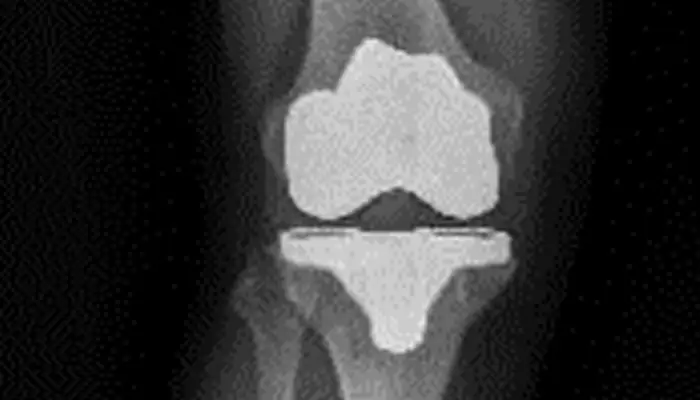

Prótesis total o parcial de rodilla (artroplastia). Consiste en la sustitución parcial o total de las superficies articulares desgastadas para restablecer la función de la rodilla.